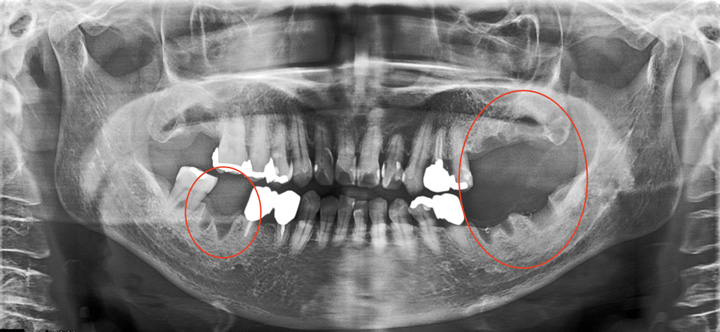

では、下のような患者様はどうでしょうか?

上の歯は前歯を中心に失っているのに対し、下の歯は奥歯を中心に失っています。このような場合を「すれ違い咬合」といって、入れ歯を作っても天然の歯による支持が不足することになるため、うまくいきません。

この場合は、インプラントを適切に配置することで、「すれ違い」を回避すれば、入れ歯を作りやすくすることが可能です。